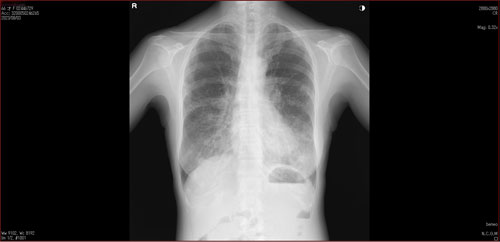

肺X線画像

- 2023.08.03 肺炎後の要観察(1)(国立系病院)